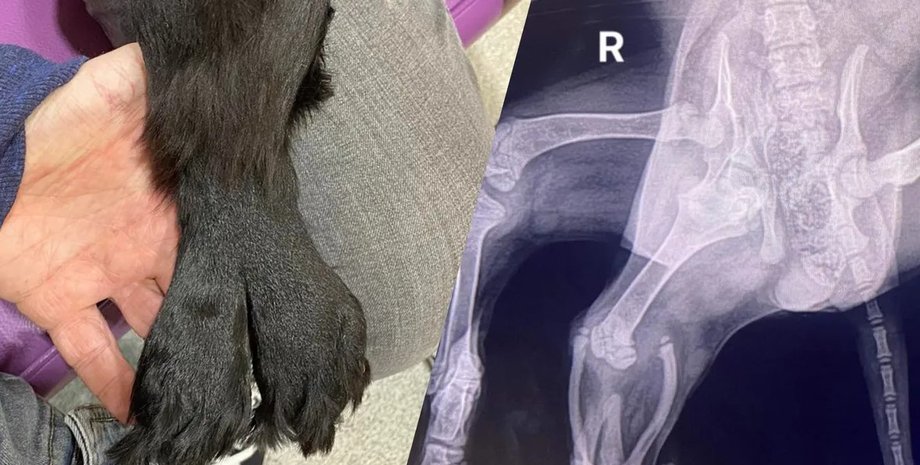

Дві додаткові кінцівки кокер-спанієля злилися разом, утворивши "хвіст русалки", але медики змогли їх видалити без шкоди тварині.

Цуценя кокер-спанієля народилося з множинними вродженими дефектами й було покинуте власниками у віці всього 11 тижнів. Серед вроджених дефектів тварини також були дві додаткові задні кінцівки, які зрослися та утворили щось на зразок "хвоста русалки", пише IFLScience.

На щастя, цуценя врятували й назвали Аріель на честь русалки. Тепер вона успішно перенесла операцію, внаслідок якої лікарі видалили дві зайві кінцівки. За словами засновника і менеджера Greenacres Rescue Майкі Лоулора, наявність двох тазостегнових суглобів з одного боку не дозволили тазу сформуватися належним чином. У результаті нормальна задня права нога тварини майже не мала мішечного тонусу.

Тоді ветеринари подумали, що зрощені ноги собаки нагадують хвіст русалки — звідси та з'явилося ім'я. Згодом виявилося, що додаткові ноги тварини не функціональні, а тому потрібна була операція.

Спочатку було оголошено збір на операцію — загалом вдалося зібрати 19 000 доларів, після цього операцію було успішно проведено. За словами дослідників із Бристольського університету, складність процедури полягала в тому, що для її проведення було потрібне широке коло фахівців, зокрема хірургів, а також радіологів і анестезіологів.

Перед операцією дослідники побоювалися, що задню лапу Аріель доведеться видалити, але, на щастя, цього не знадобилося. Хірургам вдалося не зачепити важливих нервів і кровоносних судин у задніх кінцівках, а тому задня нога Аріель залишилася максимально функціональною.